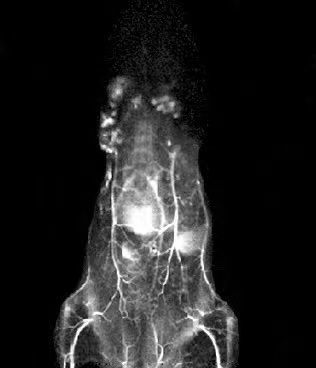

NIRVivo-MIX小动物活体荧光成像系统,覆盖 400 - 1700nm 全谱段成像,兼容了从可见光,近红外一区到近红外二区的全谱段小动物荧光成像应用的需求,能满足不同实验对不同光谱范围的要求。能降低光散射与组织自发荧光干扰,实现高分辨率与信噪比成像。它配置 808nm 、980nm、1064nm等多种波长激光器,并可以同时安装16片滤光片。相机采用 TE4 制冷,可低至 -90℃,降低噪声。软件支持自动校正等操作,界面全中文。该系统能对小鼠等动物成像,监测荧光药物,助力肿瘤检测、药物研发等工作 。

评价小动物活体荧光成像系统的关键要素——所选用相机的性能水平。NirVivo系列采用深度制冷型科学级相机产品,CCD制冷温度可达-90℃,InGaAs制冷温度可达-80℃,有效曝光时间可达60分钟*。基于良好的硬件配置,系统具备了高灵敏度的生物发光及荧光成像性能。通过搭配不同的光学系统,可以实现微区成像和血管动态成像。* CCD制冷至-90℃条件下。